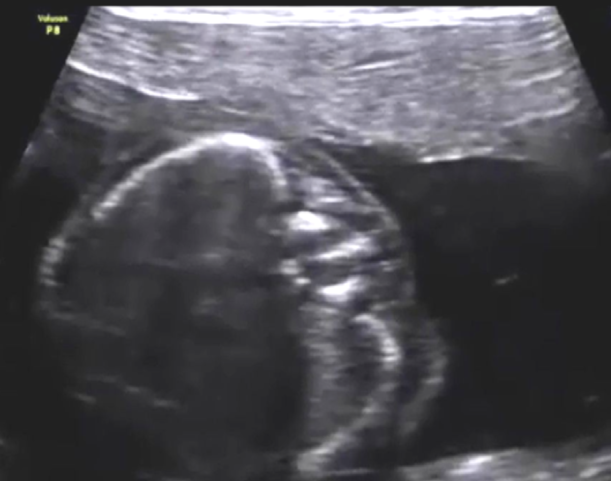

Imaging studies: This routine transabdominal obstetric sonography was performed to exclude any congenital fetal anomalies. The patient had not undergone any sonographic study prior to this scan. The images seen in Figure 1, Figure 2, and Figure 3 show the coronal section of the fetal spine and were taken during this routine sonographic examination.

In Figures 1, 2, and 3, the volume of amniotic fluid appears normal. The fetal abdomen also shows no significant abnormality. The placenta is fundic and posterior. No retroplacental hematoma is seen.

The most prominent anatomy in these images is the fetal spine. The fetal head is to the left of the images, and the fetal lower limbs are to the right of the images. The upper cervical and thoracic spines appear normal. However, there is an abnormality within the lower thoracic vertebrae that appears as an echogenic lesion within the spinal canal. It looks linear and extends within the mid-portion of the spinal canal. We cannot further distinguish the abnormality in this region. What are the diagnostic possibilities based on these images, at this stage?

After studying the aforementioned images, there is no obvious herniation of the meninges through a dorsal or ventral defect in the spine. However, there is an obvious anomaly visible in the images of the axial section of thoracic vertebrae, which was also visible in the images of the coronal section of the thoracic vertebrae. The anomaly is some form of division of the spinal canal.

True diplomyelia is characterized by near-total division of the spinal cord, which is not the case here. The division is localized to the affected lower thoracic spines. In addition, there is a vertical echogenic, possibly bony, septum within the affected thoracic vertebrae. This finding suggests the possibility of diastematomyelia. This condition is seen as a partial or complete bony septum or fibrous septum that divides the spinal canal (localized to affected spine), with partial division of the spinal cord in the affected parts only.